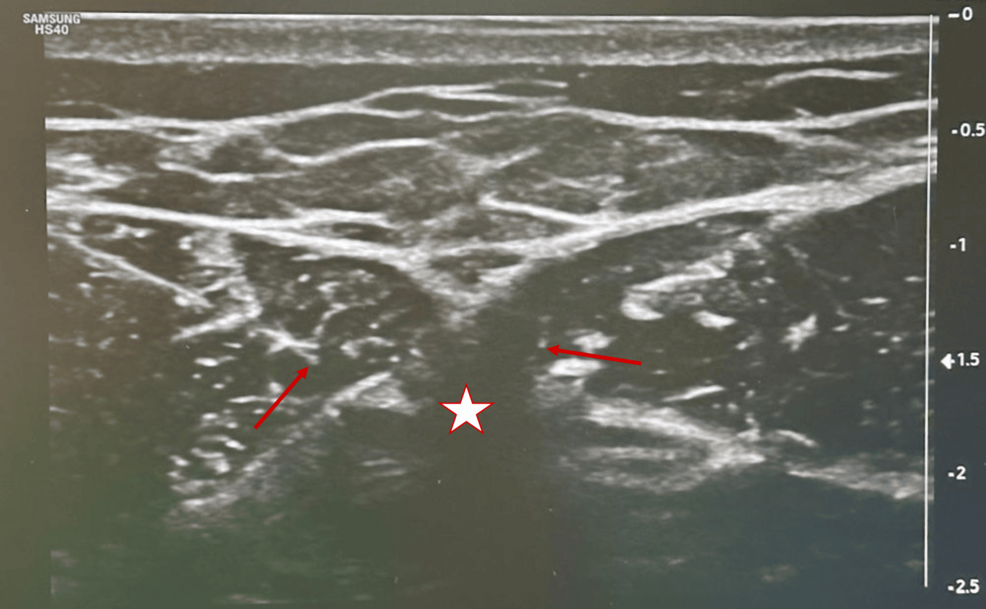

The procedure was performed six weeks after the consultation. The patient was positioned supine with his arms by his sides. A high-frequency linear ultrasound probe was used to identify the xiphoid process along with adjacent anatomical landmarks (including the costal margins and the sternal body). After appropriate skin antisepsis and local anesthesia with 1% lidocaine at the needle entry sites, an in-plane transverse approach was adopted.

Two 22 G radiofrequency needles (10 cm in length with a 10 mm active tip) were advanced under real-time ultrasound guidance so that their tips lay on either side of the xiphoid process. The inter-electrode distance was maintained at less than 10 mm to ensure effective energy delivery. Sensory testing was then performed: a positive response was recorded at stimulation levels of less than 0.5 V, while motor stimulation remained negative up to 2 V. These parameters provided confirmation of accurate needle placement targeting the sensory branches of the lower intercostal nerves.

Following successful sensory testing, bipolar pRF was administered with the following technical parameters: maximum temperature of 40°C, frequency of 2 Hz, voltage of 45 V, pulse duration of 20 ms, alternating polarity, in three cycles of two minutes (total six minutes) (Figure 1).